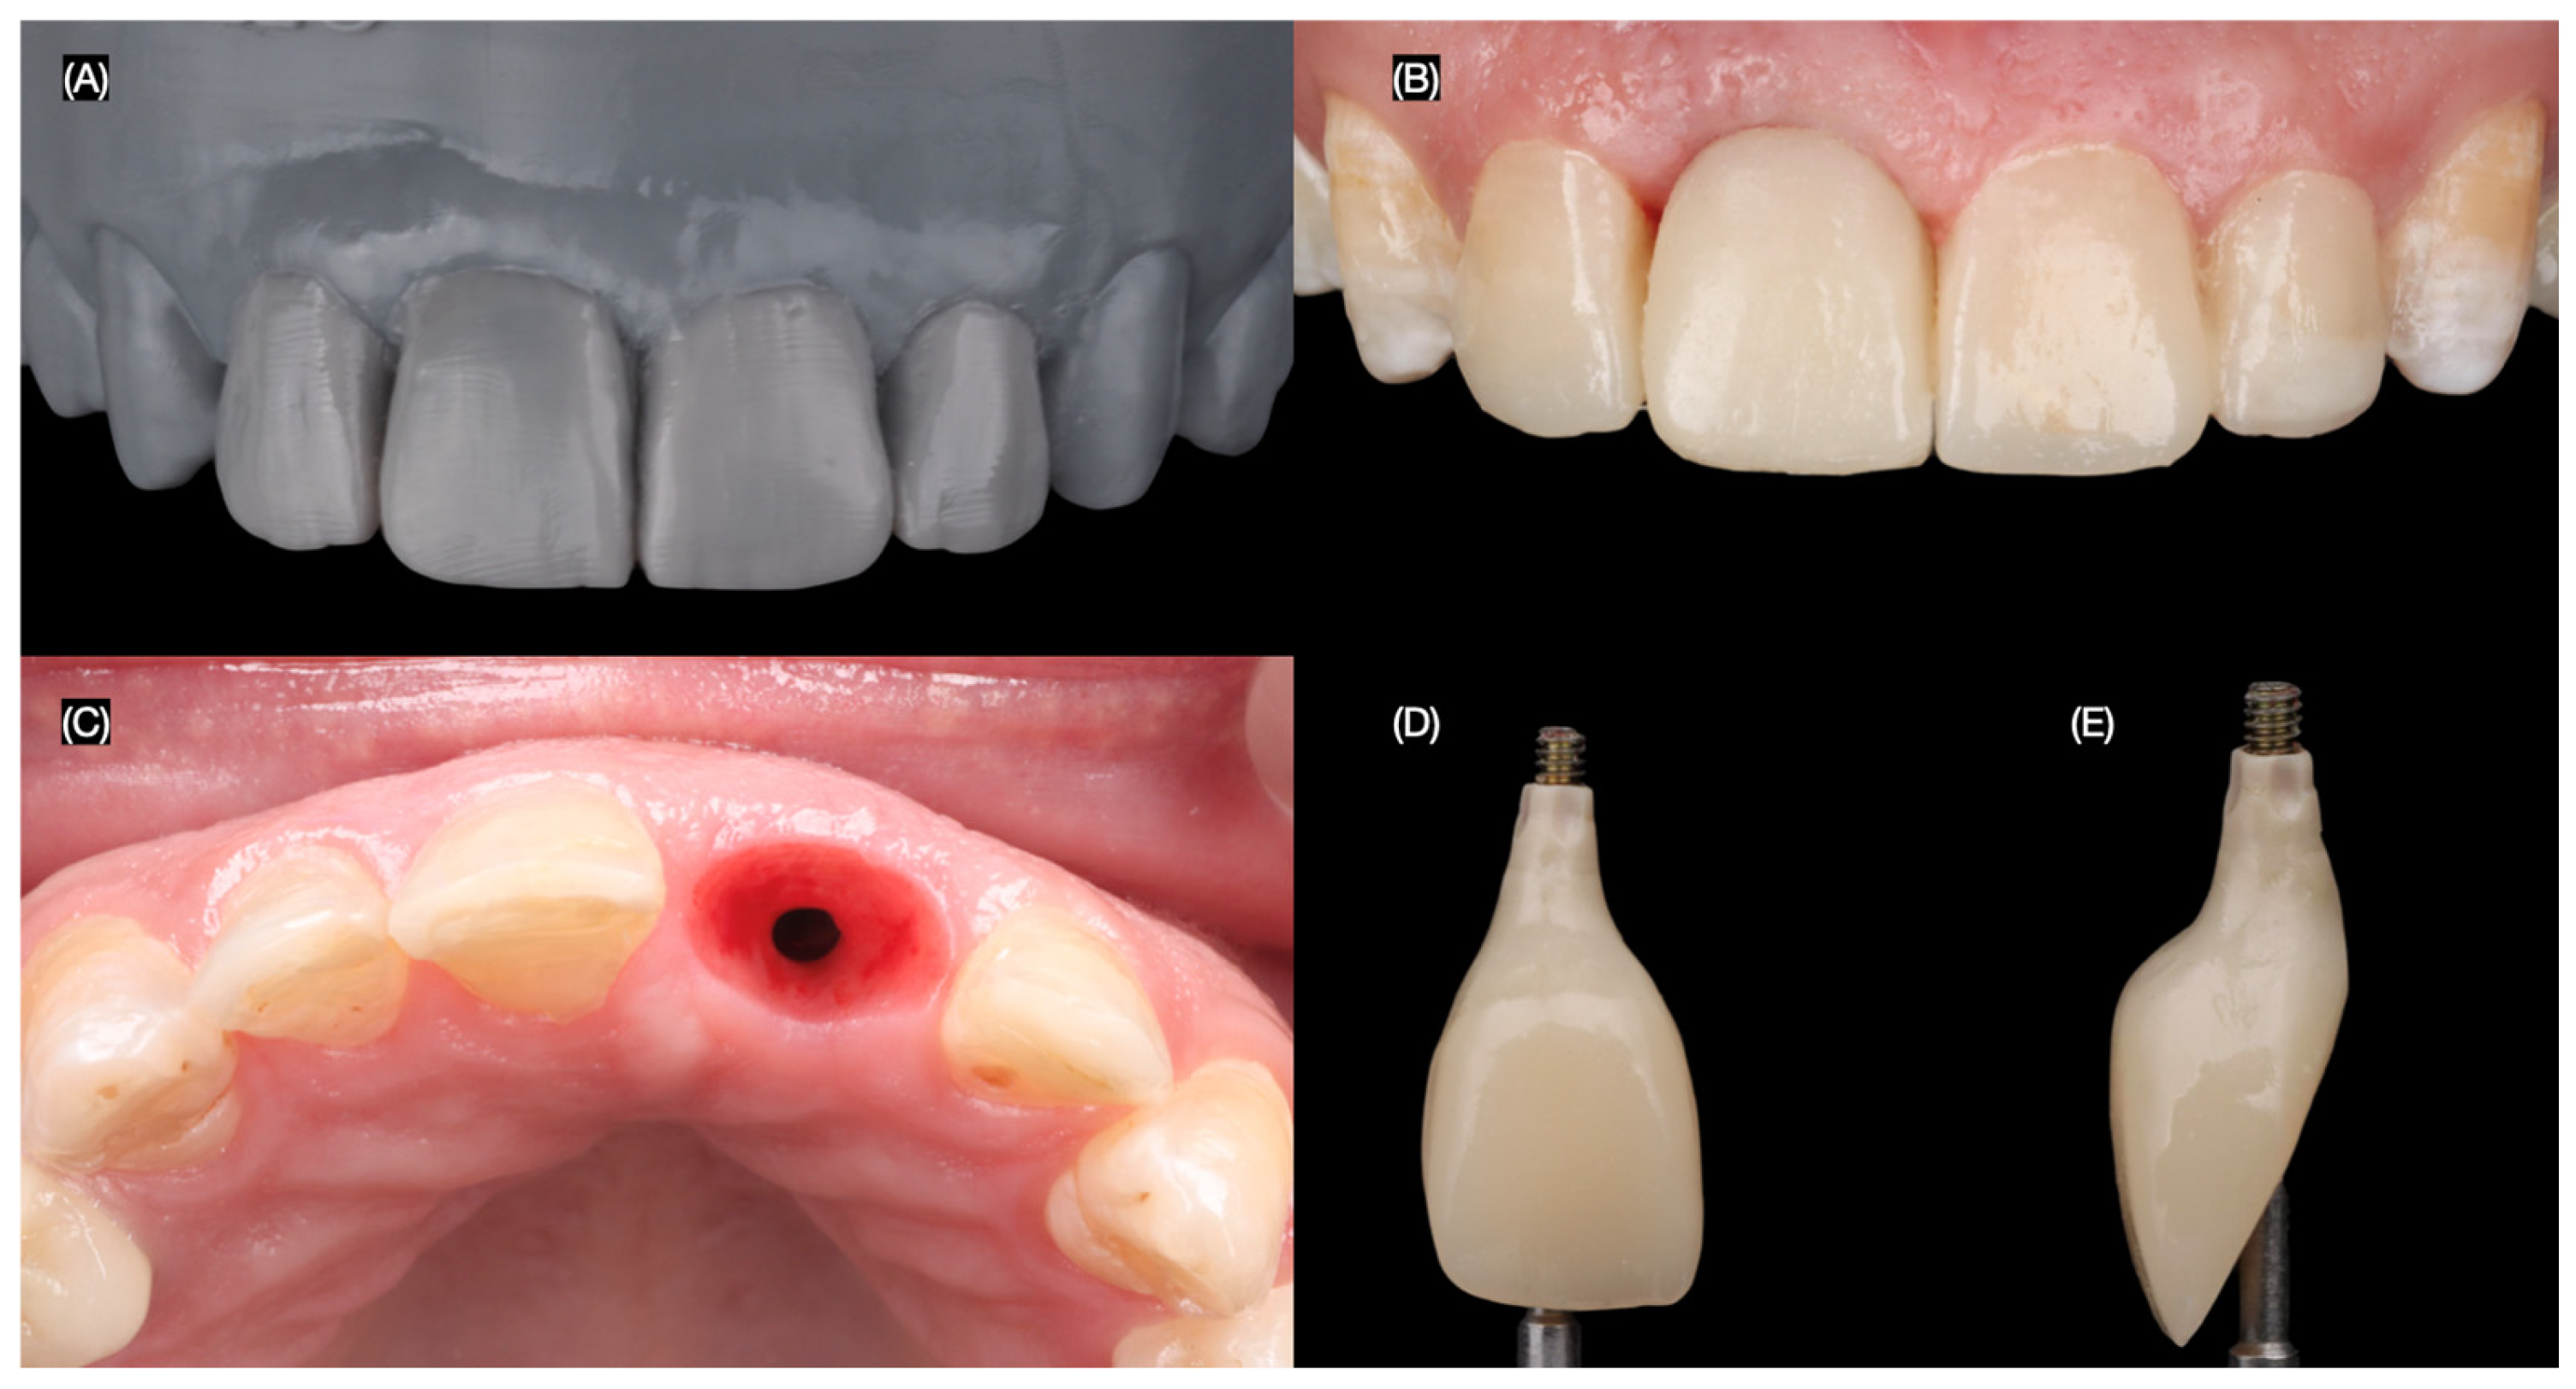

To optimize the esthetic outcome, the provisional restoration was recontoured to guide the development of the desired gingival architecture and soft tissue healing. Minimally invasive veneer preparations were then performed on the adjacent teeth using tooth reduction guides (Elite P&P, Zhermack, Badia Polesine, Italy) created from the diagnostic wax-up. These guides ensured precise and conservative tooth reduction to achieve optimal veneer fit and esthetics. A final impression of the implant and prepared teeth was made to fabricate the definitive restorations (Figure 7).

Figure 7.

Design of the final restorations. (A) Diagnostic wax-up, (B) new interim restoration, (C) soft tissue contoured, and (D) facial and (E) proximal view of interim restoration.